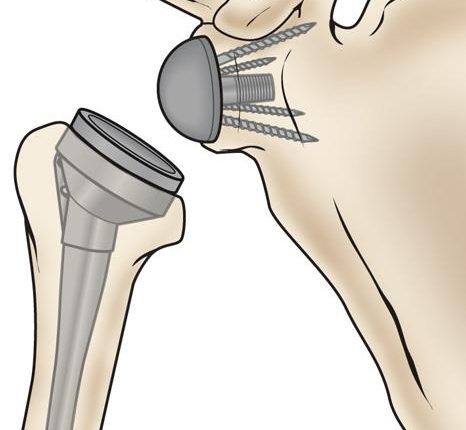

گاهی آسیبهای شانه سبب جابهجاشدن استخوانها یا شکستگی باز میشود و استخوان از پوست بیرون میزند. در چنین شرایطی متخصص ارتوپد، برای ترمیم شکستگی استخوان، رباط، ماهیچههای آسیبدیده و تاندون شانه باید جراحی انجام دهد. جراح از ابزارهای تخصصی مانند داربستهای صفحهای، پیچ یا میلههای فلزی استفاده میکند تا استخوانها را در موقعیت مناسب ثابت نگه دارد. موارد شدیدتر ممکن است نیاز به تعویض مفصل داشته باشد.

‣ عمل جراحی تعویض مفصل شانه جزئی

برای بیماری با شکستگی شدید استخوانی ممکن است عمل تعویض جزئی شانه انجام شود. برای این منظور از وسیلۀ تعویض شانه معمولی، متشکل از یک توپ و ساقه فلزی، استفاده میکنند. بخش گرد توپمانند جایگزین قسمت فوقانی استخوان بازو میشود. پس از عمل تعویض جزئی شانه احساس درد آرام میگیرد و عملکرد شانه و دامنه حرکتی مفصل بهبود مییابد.

‣ عمل جراحی تعویض کامل مفصل معکوس شانه

روش این نوع جراحی شکستگی استخوان شانه جالب است. برخلاف حالت طبیعی که قسمت گرد انتهای استخوان بازو در سوکت کتف قرار میگیرد، هنگام جراحی تعویض مفصل معکوس توپ فلزی به سوکت وصل میشود. قسمت انتهای استخوان بازو هم به حالت فنجانیشکل درمیآید تا مفصل دامنه حرکتی لازم را به دست آورد. در نهایت این روش باعث تسکین درد و بهبود عملکرد و تحرک شانۀ بیمار میشود.

در این عمل جراحی شکستگی شانه ابتدا قطعات استخوانی به محل طبیعی خود بازگردانده میشوند. سپس با اتصال صفحههای فلزی با پیچهای خاص به سطح بیرونی استخوان قطعههای جداشده در کنار هم قرار میگیرند.